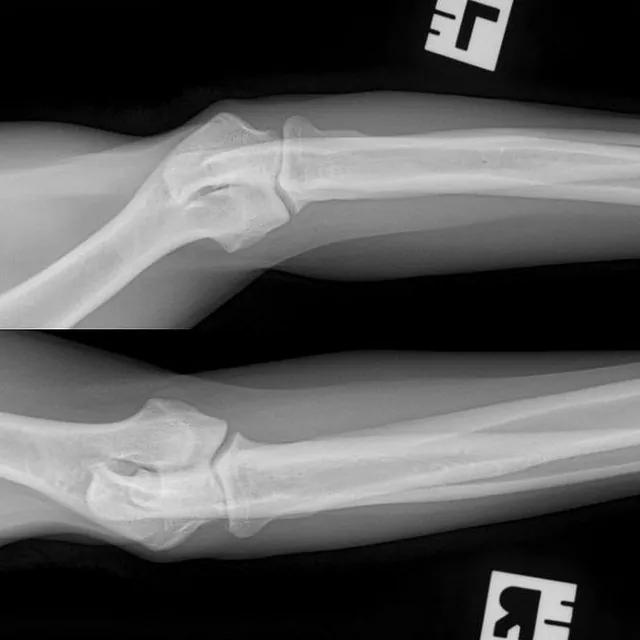

Hieronder foto's van Guus genomen met onze nieuwe DRgem rontgen. Beoordeeld met de hoogste score door de Raad van Beheer op Kynologisch gebied

Elleboogdysplasie (ED) onderzoek

Elleboogdysplasie is een ontwikkelingsstoornis van de ellebooggewrichten, met name het kraakbeen is aangetast. Deze aandoening kan erfelijk zijn, maar omgevingsfactoren spelen soms ook een rol. Er zijn honden die op jonge leeftijd al problemen ondervinden door ED, soms komt het pas op latere leeftijd tot uiting. Om te kunnen zien of uw hond ED heeft zijn röntgenfoto’s van de ellebogen nodig.

Voor een aantal rassen is een diagnose-onderzoek verplicht. Bij dit onderzoek dienen er per elleboog vier foto’s in vier verschillende richtingen gemaakt te worden (dus in totaal 8 foto’s). Deze rassen zijn: Labrador Retriever, Golden Retriever, Chesapeake Bay Retriever, Rottweiler, Berner Sennenhond, Duitse Herdershond, Bordeaux Dog.

Voor alle andere rassen volstaat een onderzoek met twee foto’s per elleboog. Meestal passen wij een lichte sedatie toe bij het maken van de officiële ED-foto’s. Dit is nodig om een kwalitatief goede foto te maken, welke aan de hoge eisen van de beoordelingscommissie moet voldoen. Uw hond moet op zijn of haar zijde en borst liggen, waarbij de elleboog in verschillende houdingen wordt gelegd.